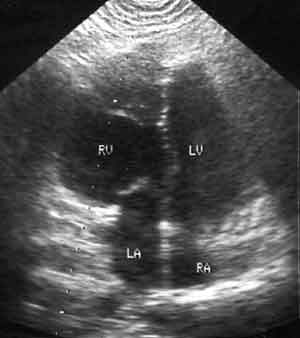

Случай коррегированной транспозиции магистральных сосудов.

Рис. 3. При Эхо-КГ-исследовании изображение, полученное из четырехкамерной позиции, позволило заподозрить инверсию желудочков.